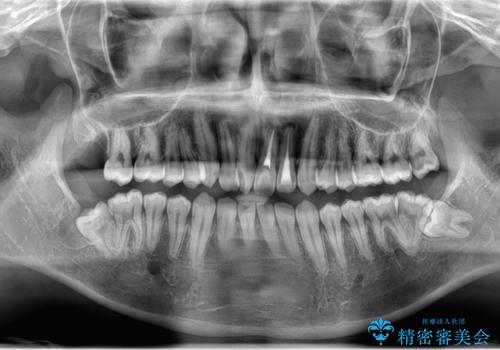

- 右上下親知らずを抜きたいとの事で来院。

レントゲンを確認したとこと完全埋伏歯でした。

CTで神経の位置などを確認し、抜歯術を行いました。

無事抜歯を行うことができました。